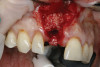

Based on the single extraction socket roadmap developed by El Chaar and colleagues, the socket of tooth No. 8 was diagnosed as Grade III and would require initial treatment that included the extraction of failing tooth No. 8 followed by simultaneous guided bone regeneration and soft-tissue augmentation by means of a rotated palatal pedicle flap (Figure 8 through Figure 11).27,28 The principles of and guidelines for both the ridge augmentation and rotated pedicle flap have been described in the literature and will not be focused on in this case report.27-30 The patient was temporized with a bonded Maryland bridge that was adjusted to avoid creating pressure on the tissue during healing (Figure 12).

8. Tooth No. 8 with diagnosis of Grade III socket, requiring extraction followed by guided bone regeneration and a rotated pedicle flap to gain hard and soft tissue for future implant placement.

Figure 8

9. Tooth No. 8 with diagnosis of Grade III socket, requiring extraction followed by guided bone regeneration and a rotated pedicle flap to gain hard and soft tissue for future implant placement.

Figure 9

10. Tooth No. 8 with diagnosis of Grade III socket, requiring extraction followed by guided bone regeneration and a rotated pedicle flap to gain hard and soft tissue for future implant placement.

Figure 10

11. Tooth No. 8 with diagnosis of Grade III socket, requiring extraction followed by guided bone regeneration and a rotated pedicle flap to gain hard and soft tissue for future implant placement.

Figure 11